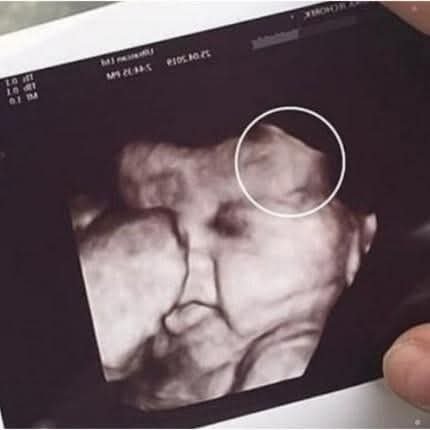

routine prenatal checkup took an unexpected turn for one mother after she grew visibly anxious during her daughter’s ultrasound appointment. According to witnesses at the clinic, the

mother had accompanied her daughter for support but became increasingly uneasy as the technician prepared to reveal the scan. What was supposed to be a joyful moment quickly shifted into uncertainty when the medical staff paused to take a closer look at the monitor.

technician, maintaining calm professionalism, informed the family that the image had shown something unusual that required further evaluation. While they did not immediately disclose details, the brief silence in the room left both mother

and daughter unsettled. Staff assured them that unclear images are common—ultrasounds can sometimes capture shadows, angles, or movements that look concerning but turn out to be harmless upon review READ MORE BELOW